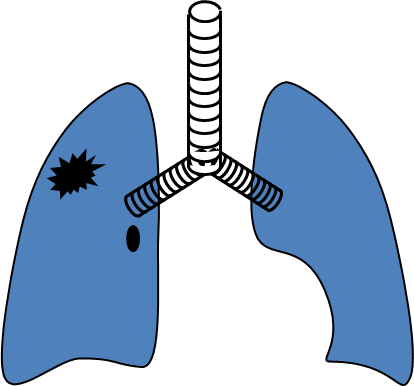

Şəkil 10. Ağciyər absesinin yaranma mexanizmləri və gedişi

Klinik təsnifatda ağciyər xərçəngi 3 mərhələyə bölünür:

- Erkən mərhələ - mediastinal yayılma yoxdur (I-II mərhələlər)

- Yerli yayılmış mərhələ - mediastinuma yayılma var (IIIA və B mərhələlər)

- Metastaz mərhələsi - distal metastazlar var (IV mərhələ) (Şəkil 10).